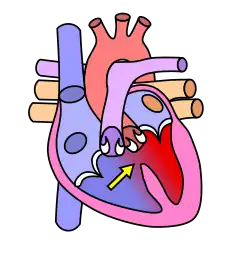

Heart Chambers

The heart has four chambers, two atria and two ventricles. The atria are smaller with thin walls, while the ventricles are larger and much stronger.

Atrium

There are two atria on either side of the heart. On the right side is the atrium that contains blood which is poor in oxygen. The left atrium contains blood which has been oxygenated and is ready to be sent to the body. The right atrium receives de-oxygenated blood from the superior vena cava and inferior vena cava. The left atrium receives oxygenated blood from the left and right pulmonary veins. Atria facilitate circulation primarily by allowing uninterrupted venous flow to the heart, preventing the inertia of interrupted venous flow that would otherwise occur at each ventricular systole.

Ventricles

The ventricle is a heart chamber which collects blood from an atrium and pumps it out of the heart. There are two ventricles: the right ventricle pumps blood into the pulmonary artery which takes the blood through the pulmonary circuit, and the left ventricle pumps blood into the aorta for systemic circulation to the rest of the body. Ventricles have thicker walls than the atria, and thus can create the higher blood pressure. Comparing the left and right ventricle, the left ventricle has thicker walls because it needs to pump blood to the whole body. This leads to the common misconception that the heart lies on the left side of the body.

Septum

Valves

The two atrioventricular (AV) valves are one-way valves that ensure that blood flows from the atria to the ventricles, and not the other way. The two semilunar (SL) valves are present in the arteries leaving the heart; they prevent blood from flowing back into the ventricles. The sound heard in a heart beat is the heart valves shutting. The right AV valve is also called the tricuspid valve because it has three flaps. It is located between the right atrium and the right ventricle. The tricuspid valve allows blood to flow from the right atrium into the right ventricle when the heart is relaxed during diastole. When the heart begins to contract, the heart enters a phase called systole, and the atrium pushes blood into the ventricle. Then, the ventricle begins to contract and blood pressure inside the heart rises. When the ventricular pressure exceeds the pressure in the atrium, the tricuspid valve snaps shut. The left AV valve is also called the bicuspid valve because it has two flaps. It is also known as the mitral valve due to the resemblance to a bishop's mitre (liturgical headdress). This valve prevents blood in the left ventricle from flowing into the left atrium. As it is on the left side of the heart, it must withstand a great deal of strain and pressure; this is why it is made of only two cusps, as a simpler mechanism entails a reduced risk of malfunction. There are two remaining valves called the Semilunar Valves. They have flaps that resemble half moons. The pulmonary semilunar valve lies between the right ventricle and the pulmonary trunk. The aortic semilunar valve is located between the left ventricle and the aorta.

Passage of Blood Through the Heart

While it is convenient to describe the flow of the blood through the right side of the heart and then through the left side, it is important to realize that both atria contract at the same time and that both ventricles contract at the same time. The heart works as two pumps, one on the right and one on the left that works simultaneously. The right pump pumps the blood to the lungs or the pulmonary circulation at the same time that the left pump pumps blood to the rest of the body or the systemic circulation. Venous blood from systemic circulation (deoxygenated) enters the right atrium through the superior and inferior vena cava. The right atrium contracts and forces the blood through the tricuspid valve (right atrioventricular valve) and into the right ventricles. The right ventricles contract and force the blood through the pulmonary semilunar valve into the pulmonary trunk and out the pulmonary artery. This takes the blood to the lungs where the blood releases carbon dioxide and receives a new supply of oxygen. The new blood is carried in the pulmonary veins that take it to the left atrium. The left atrium then contracts and forces blood through the left atrioventricular, bicuspid, or mitral, valve into the left ventricle. The left ventricle contracts forcing blood through the aortic semilunar valve into the ascending aorta. It then branches to arteries carrying oxygen rich blood to all parts of the body.